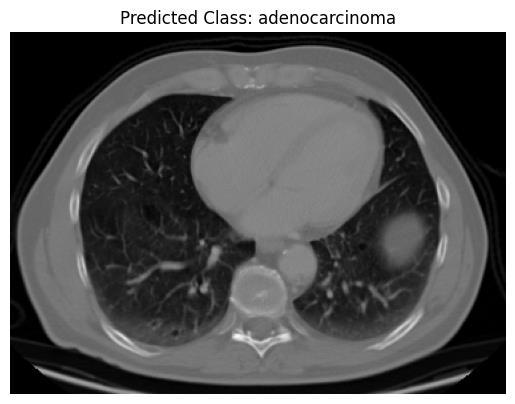

The input data includes the lung CT scan images , which havebeencollectedfrom the local hospitals.All theseCT scan images have been annotated by expert radiologists after effective analyses, ensuring high clinical accuracy. Each image is labeled as one of the four categories, includingadenocarcinoma,largecellcarcinoma,squamous cellcarcinoma,andnormallung.

The steps include: First, the image will be pre-processed, which also consists of resizing to a standard size such as 128×64 pixels, and applying grayscale. Then, calculations of gradients are done to find pixels that would change significantly in intensity, resulting into edges. Then, the image is further divided into small cell sizes (from 8 by 8 or 16 by 16 pixel sizes) for every cell producing an orientation histogram based on the gradient direction weighted by its magnitude. This process includes several steps involving group cells in overlapping blocks to normalize the histograms made invariant to variations in lightingorcontrast.Thenormativehistogramsaremerged into one vector where the numbers describe different structural features of the image. Clearly, the CT scan data has been distilled into a format that can be processed using conventional machine learning algorithms like SupportVectorMachine,LogisticRegression,orGaussian NaïveBayes,duetoitsnumericalstructure.Theclassifiers thatweretrainedandevaluatedwiththesefeaturesaimto distinguish adenocarcinomas from large cell carcinomas, squamous cell carcinomas, and lung conditions deemed normal.

Support Vector Machine (SVM), Logistic Regression, and Naive Bayes, all widely known, were used for the classificationprobleminthisresearchanalysis.Asaresult of the well-defined features obtained through methods likeHOG,themodelswereusedtoassesstheperformance of lung cancer image classification into adenocarcinoma,

large cell carcinoma, normal, and squamous cell carcinoma.